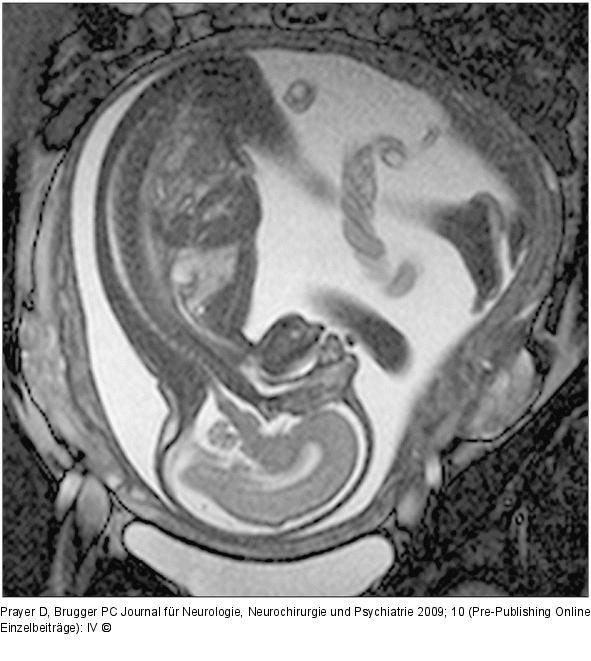

Abbildung 1: Fetus - Sagittale Schichtführung Sagittale Schichtführung durch einen Fetus in der 27. SSW. Durch das große "Field of View" kann der ganze Fetus abgebildet werden. Das Profil, einschließlich des harten und weichen Gaumens, ist beurteilbar. Intrazerebral erkennt man kortikal den Beginn der Formation der Zentralregion, Hirnstamm und Kleinhirn. Die räumliche Auflösung ist groß genug, um kleine Strukturen wie das Chiasma opticum darzustellen. Intrauterin zeigt sich darüber hinaus eine regelrechte Nabelschnur, die – im Querschnitt getroffen – 3 Gefäße aufweist. |

Abbildung 1: Fetus - Sagittale Schichtführung

Sagittale Schichtführung durch einen Fetus in der 27. SSW. Durch das große "Field of View" kann der ganze Fetus abgebildet werden. Das Profil, einschließlich des harten und weichen Gaumens, ist beurteilbar. Intrazerebral erkennt man kortikal den Beginn der Formation der Zentralregion, Hirnstamm und Kleinhirn. Die räumliche Auflösung ist groß genug, um kleine Strukturen wie das Chiasma opticum darzustellen. Intrauterin zeigt sich darüber hinaus eine regelrechte Nabelschnur, die – im Querschnitt getroffen – 3 Gefäße aufweist. |